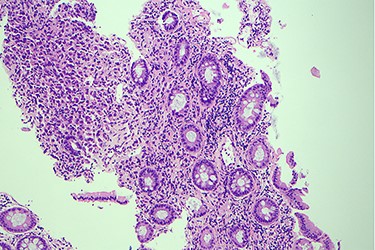

Surveillance colonoscopy in 2018 identified a fungating nonobstructing mass in the sigmoid colon (Fig. 1). Histology from a biopsy showed poorly differentiated carcinoma (Fig. 2). Given the history of breast cancer, further immunohistochemical staining was performed, which was positive for E-cadherin (Fig. 3), ER (Fig. 4), PR, GATA3 binding protein (GATA 3) (Fig. 5) and negative for Cytokeratin 20 (CK20) (Fig. 6). This confirmed metastatic invasive ductal carcinoma of breast. A positron emission tomography (PET) scan showed only the retroperitoneal mass involving the proximal sigmoid colon with no other evidence of metastatic disease (Fig. 7).

Histology slide of the biopsy with H&E staining showing poorly differentiated carcinoma.